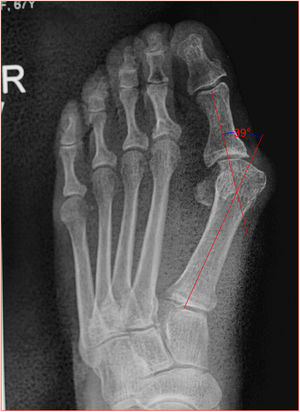

Angulo de valgo: es la intersección del ejes longitudinales del primer metatarsiano y de la falange proximal del hallux. Normal hasta 15 grados (fig. 5).